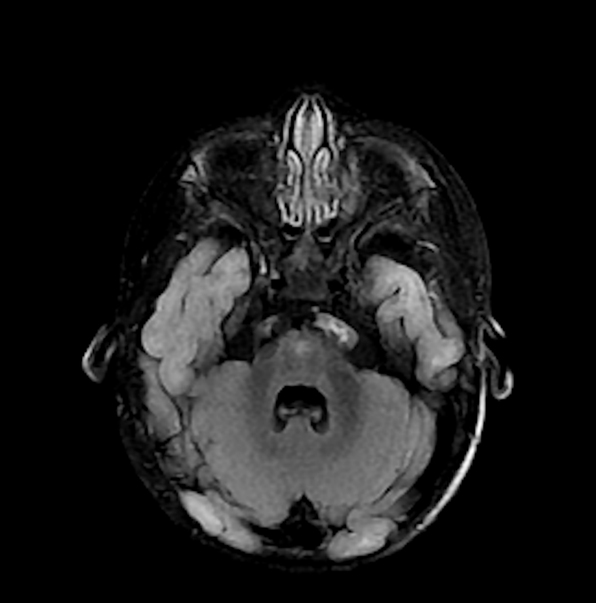

Leukoencephalopathy From SDHAF1-Related Mitochondrial Deficiency

Paul Bellissimo, Clara Nemr, Samantha Newman, Asna Tauseef, Talha Allam

1-9